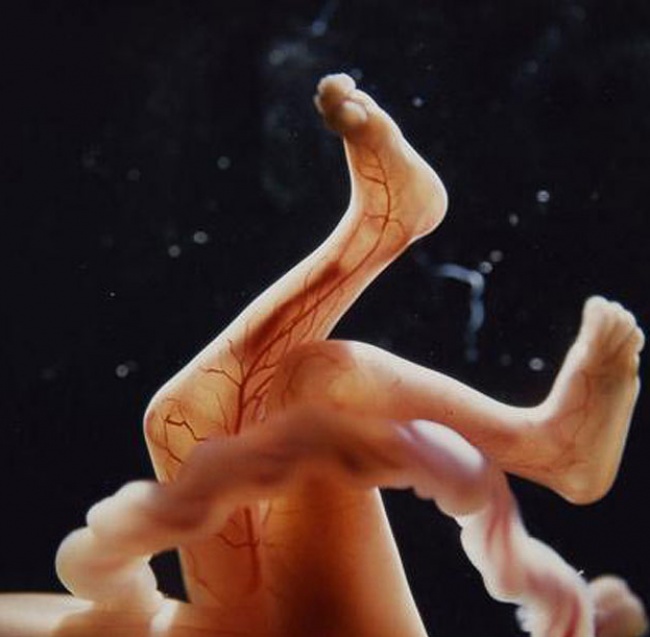

El embrión ya tiene movimiento, una bella imagen.